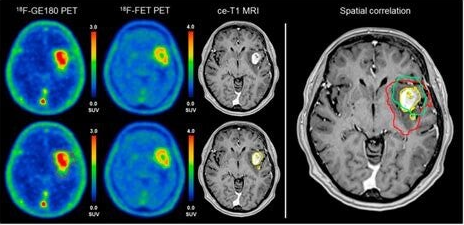

In de medische beeldvorming worden, in zeer kleine hoeveelheden, radioactieve isotopen gebruikt om een diagnose te kunnen stellen. Er wordt dan een tracer ingebracht: een radioactief isotoop die op een bepaalde plek of in ene bepaald orgaan net zo goed opgenomen wordt als het niet-radioactieve isotoop van dezelfde stof. Doordat het radioactieve isotoop gammastraling uitzendt kan met detectoren de locatie van het isotoop in beeld gebracht worden, en wanneer je het een tijdje volgt krijg je informatie over het functioneren van een orgaan of deel van het lichaam. Dit is de techniek die bijvoorbeeld in PET-scans en SPECT-scans gebruikt wordt.

PET-scan.

PET-scan van hersenen van een patiënt.